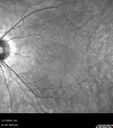

RP_anrus_071719_01.png

Retinitis Pigmentosa - Autosomal Recessive - 20/25 Vision373 views49 year old man 15 years ago he noticed decreased night vision.

VA OD: sc20/25 NscJ2

VA OS: sc20/25-2 NscJ2-1

IOP: TP: OD:17 OS:19

Genetic testing showed heterozygous for RPE65 - Probably not clinically important